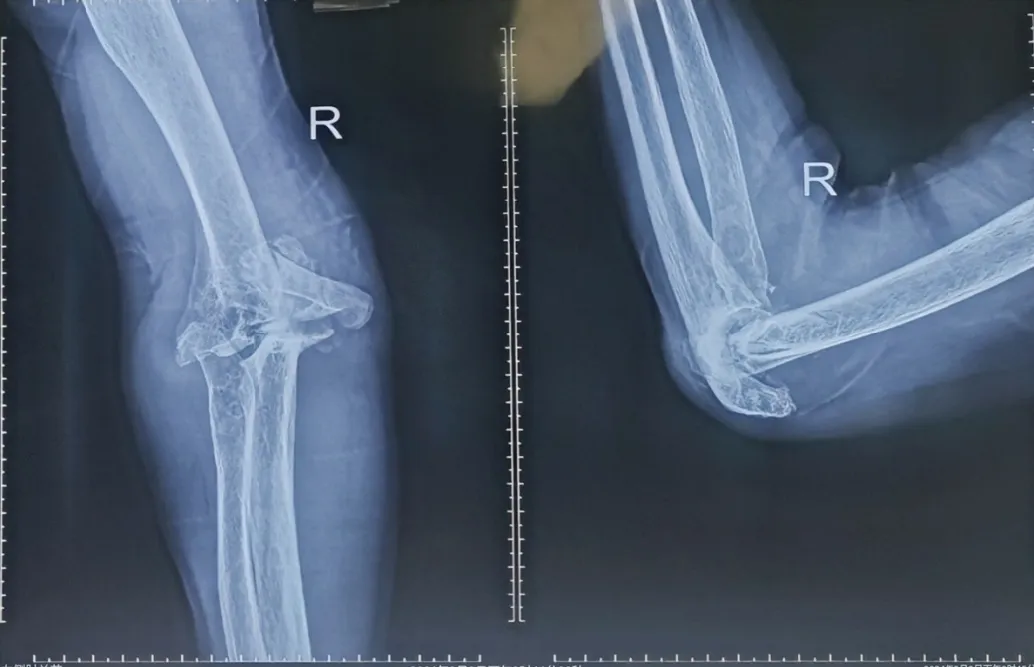

患者孙某,65岁,患者于家中不慎摔伤右上臂,患者为求进一步诊治来我院就诊,被诊断为:右肱骨髁间骨折、右上尺桡关节脱位、肝血管瘤、单纯性肾囊肿。另外,患者有类风湿病史38年。手术治疗的目的是尽最大限度恢复肘关节的功能。

患者术后X光片